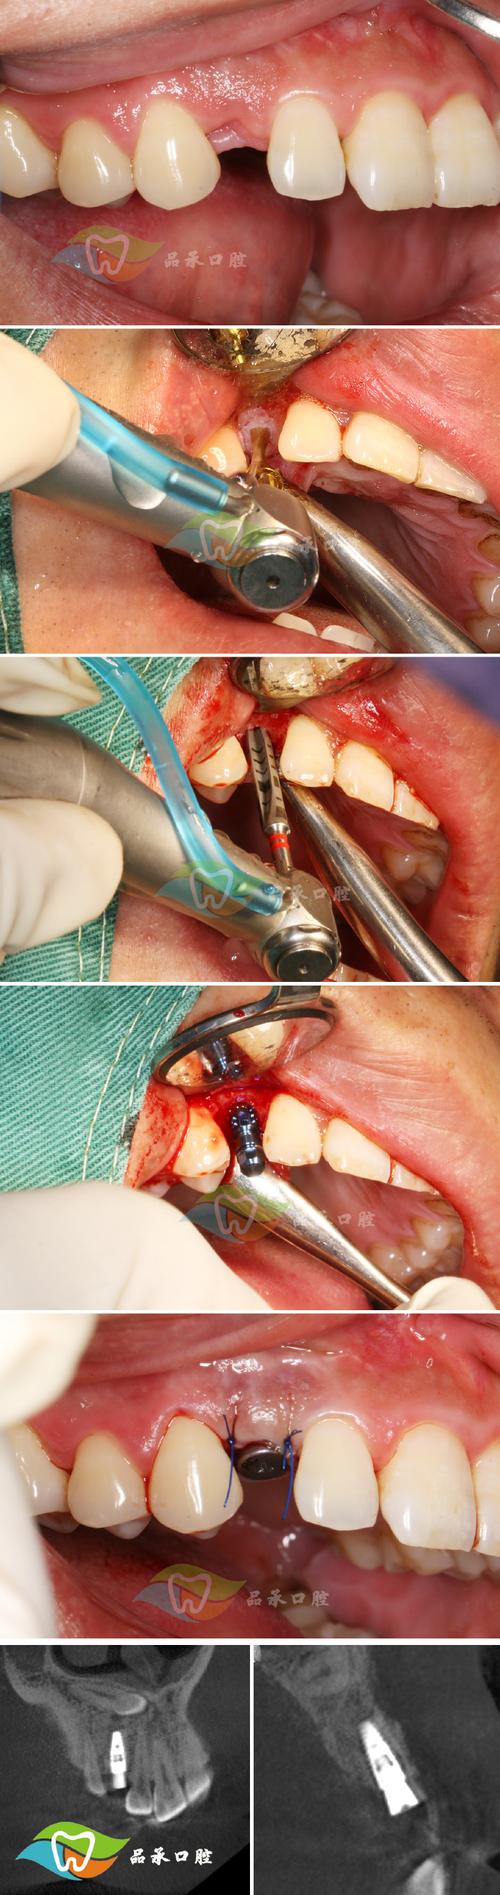

手术操作步骤精细,需在局部浸润麻醉或全身麻醉下进行:首先彻底清创,去除缺损区的炎性肉芽组织和瘢痕;然后根据缺损大小和形态,制备植骨床,确保受植区骨面有新鲜血液渗出,利于骨细胞附着;接着处理植骨材料,若为自体骨,需从供骨区获取(如髂骨块松质骨或下颌骨外板皮质骨),注意保留骨细胞的活性;异体骨或人工骨则需复温或预处理;随后将植骨材料紧密植入缺损区,必要时使用钛板、钛钉等固定,防止移位;最后分层缝合黏膜,关闭创口。

术后愈合阶段是骨再生关键,植骨材料需与受植区骨组织通过“爬行替代”或“直接愈合”实现骨整合,自体骨愈合周期约3-6个月,异体骨或人工骨可能需6-9个月,期间需避免植骨区受力,定期复查CBCT评估骨形成情况,待骨密度和骨量达标后,再进行二期种植体植入手术。